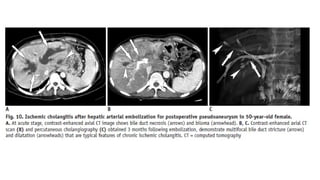

Ischemic Cholangitis

• Ischemic cholangitis is defined as ischemia-induced bile duct injuries due to various causes.

The bile ducts are vulnerable to ischemic injuries as the blood supply to the bile ducts

depends completely on the arterial supply in contrast to the hepatic parenchyma, which has a

dual blood supply from the hepatic artery and the portal vein

• Among the various conditions that compromise the arterial supply and can cause ischemic

cholangitis, iatrogenic causes including liver transplantation, hepatic arterial infusion of

chemotherapeutic agents, and vessel injury during biliary or pancreatic surgery constitute the

most common etiology

• At the acute stage of ischemic cholangitis, the patients usually present with fever, abdominal

pain, jaundice, and biliary sepsis. At this stage, the radiologic findings of biliary casts include

intraductal filling defects in the dilated bile duct showing high signal intensity on

nonenhanced T1-weighed MR images . At the acute stage of ischemic cholangitis, biliary casts

appear similar to intraductal stones. However, they usually differ in their shapes, as biliary

casts appear linear or have a branching pattern, whereas stones are usually oval or round . In

severe ischemic injury, bile duct necrosis presents as tubular low density or intensity

structures along the portal tracts on enhanced CT or MR images